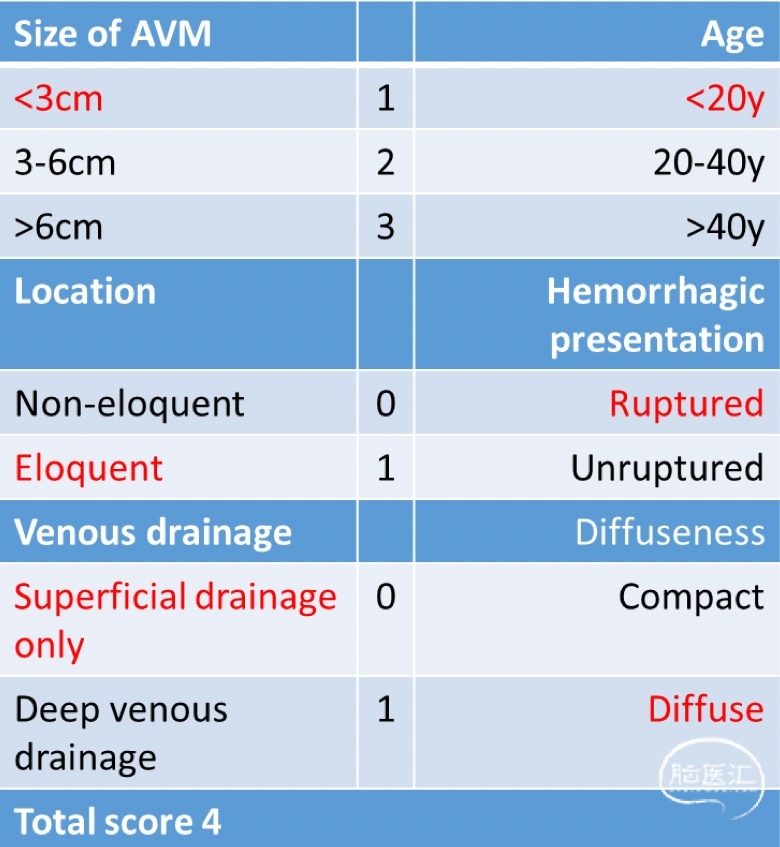

●Spetzler-Martin分级2级;Lawton-Young分级2级;总分4分。

供血动脉较细,畸形团弥散,栓塞治疗较为困难。根据Spetzler-Martin及Lawton-Young分级,总分4分,适合手术治疗。